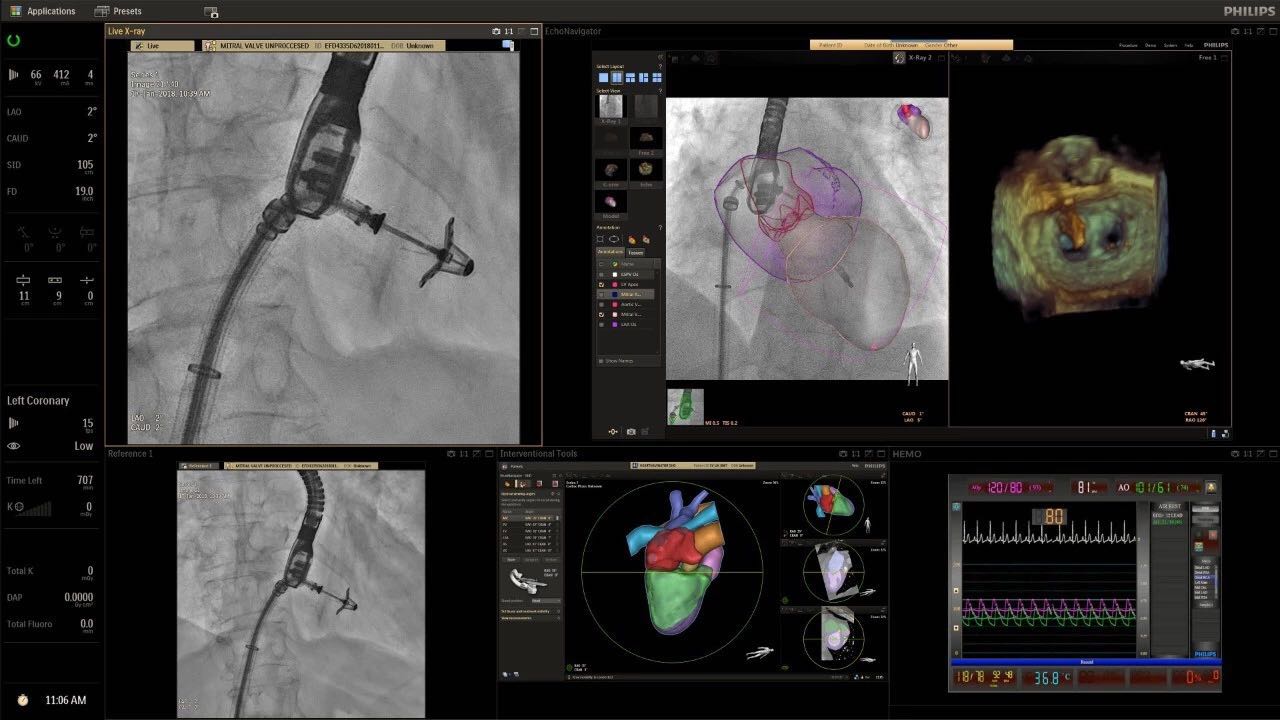

在日益復(fù)雜的干預(yù)期間,臨床醫(yī)生需要快速、輕松地可視化關(guān)鍵解剖結(jié)構(gòu)并確定手術(shù)過程中患者的變化。2019年1月17日,飛利浦宣布推出采用FlexArm的Azurion 7 C20,旨在提高圖像引導(dǎo)程序的定位靈活性。

帶有FlexArm的Azurion 7 C20 包含一系列創(chuàng)新技術(shù),使臨床醫(yī)生可以更輕松地在整個患者身上進(jìn)行二維和三維成像。當(dāng)臨床醫(yī)生移動系統(tǒng)時,圖像光束自動保持與患者的對準(zhǔn),允許更一致的可視化并使他們能夠?qū)⒆⒁饬性谥委熒稀?/span>

“憑借FlexArm,飛利浦的工程師已經(jīng)克服了幾乎不可能的幾何和機(jī)械障礙,使臨床醫(yī)生能夠在圖像引導(dǎo)治療方面實現(xiàn)臨床卓越,”邁阿密心臟與血管研究所創(chuàng)始人兼首席醫(yī)療主管Barry T. Katzen博士說?!癋lexArm使我們能夠大大優(yōu)化患者周圍的程序,我們可以最佳地了解患者體內(nèi)的情況,而不會妨礙所有在桌面上工作的臨床醫(yī)生。結(jié)果是一項不僅具有臨床重要性,而且使用起來非常簡單直觀的創(chuàng)新。這是復(fù)雜手術(shù)過程中的一個關(guān)鍵因素?!?

可通過微創(chuàng)手術(shù)治療的疾病的范圍和復(fù)雜性繼續(xù)擴(kuò)大。相應(yīng)地,程序本身也變得更加復(fù)雜,需要來自不同學(xué)科的更多醫(yī)生在患者的桌邊,以高度協(xié)調(diào)的方式一起工作。因此,臨床團(tuán)隊需要在高度受限的環(huán)境中執(zhí)行越來越具有挑戰(zhàn)性的程序。

飛利浦表示,采用FlexArm設(shè)計的Azurion 7 C20可提供卓越的靈活性和直觀的控制。該系統(tǒng)由智能運動引擎驅(qū)動,可在八個不同的軸上移動,所有這些軸均由其單個“Axsys”控制器控制。臨床醫(yī)生的模擬測試表明,該系統(tǒng)有可能顯著減少患者,工作人員和設(shè)備的重新定位,從而改善微創(chuàng)手術(shù)的可及性,包括通過患者手腕進(jìn)入身體的手術(shù)(橈動脈入路),并降低患者的風(fēng)險。無意中拔出電線和管子,以及節(jié)省大量時間。該系統(tǒng)非常適合混合手術(shù)室(OR),可滿足一個房間內(nèi)的多種專業(yè)需求,例如手術(shù)和血管內(nèi)手術(shù)的組合。

FlexArm在不少于8軸的情況下旋轉(zhuǎn),從而創(chuàng)建幾乎無限的靈活性來執(zhí)行成像,從頭部到腳部在左側(cè)和右側(cè)進(jìn)行2D和3D可視化。圖像光束保持與患者對齊,允許在旋轉(zhuǎn)或角度期間更好地可視化解剖結(jié)構(gòu)。使用Axsys運動控制系統(tǒng)輕松操作支架。